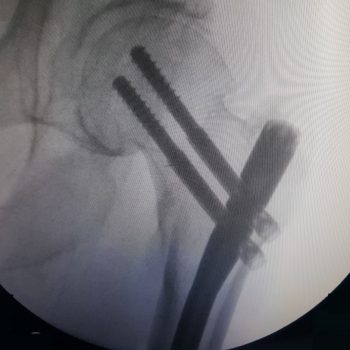

Proximal Femoral Nail

PFN

Lag mixlari va Intramadul Femur mixlari